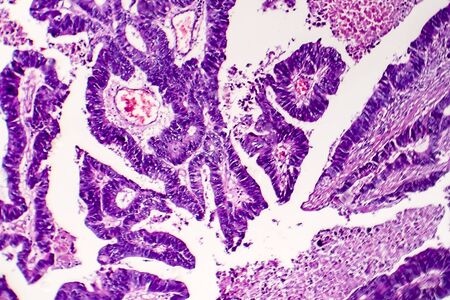

Papillary serous ovarian adenocarcinoma, cancer of ovary, light micrograph, photo under microscope